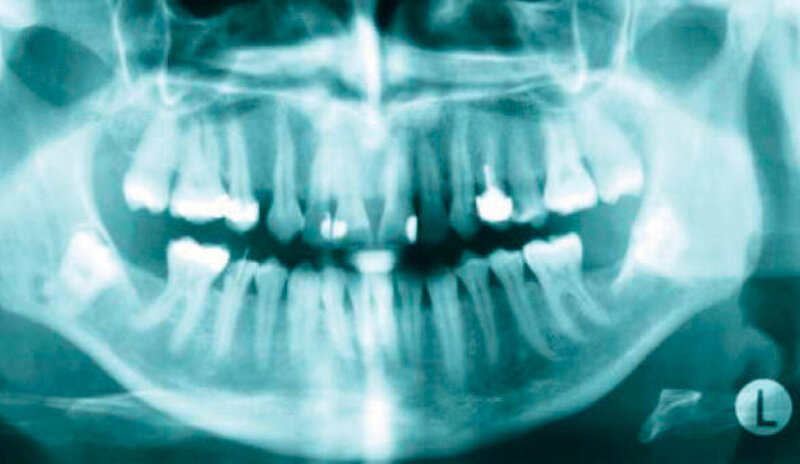

Eine 47-jährige Patientin wurde zur Entfernung der komplett retinierten Zähne 38 und 48 überwiesen. An der Wurzelspitze des Zahnes 48 fiel zusätzlich eine periradikuläre Transluzenz auf, die zur Indikationsstellung der Entfernung der Zähne führte (Abbildungen 1 und 2).

In der aus der digitalen Volumentomografie herausgerechneten Panoramaschichtaufnahme analogen Darstellung kann man schön die Alteration des Nervverlaufs in unmittelbarer Nachbarschaft zu den Weisheitszähnen erkennen. Der Nerv taucht von proximal kommend noch hinter dem Zahn liegend in die Tiefe, um dann auf Höhe der distalen Wurzel wieder in einem geraden Verlauf nach vorne weiter zu ziehen.

In der 3-D-Aufnahme bestätigte sich der Verdacht, dass der Nerv zwischen den Wurzeln hindurch zog, wobei beim Zahn 48 die Wurzeln den Nerv komplett umklammerten (Abbildungen 3 und 4). Nach Inzision auf dem aufsteigenden Unterkieferast mit Entlastung an den Zähnen 37 beziehungsweise 47 wurden der Knochen und im Weiteren die Weisheitszähne dargestellt. Die Kronen wurden von der Wurzel getrennt, die Wurzeln separiert und sukzessive entfernt, wobei die Integrität der Nerven auf beiden Seiten erhalten blieb (Abbildung 5).

Eine Verletzung des Nervus alveolaris inferior bei Weisheitszahnentfernung findet sich überproportional häufig in Fällen, in denen auf der Panoramaschichtaufnahme Zeichen zu erkennen sind, wie eine Veränderung des Verlaufes des Nervus alveolaris inferior (Abbildungen 1 und 2), bei überlagerungsbedingter erhöhter Transluzenz im Bereich der Überprojektion von Wurzel und Nerv und bei Unterbrechung der kortikalen Begrenzung des Nervkanals [Blaeser et al., 2003]. Alle diese Kriterien lagen im vorliegenden Fall vor. In der weiterführenden digitalen Volumentomografie ist zu erkennen, wie der Nerv zwischen den Wurzeln liegend hindurchzieht.